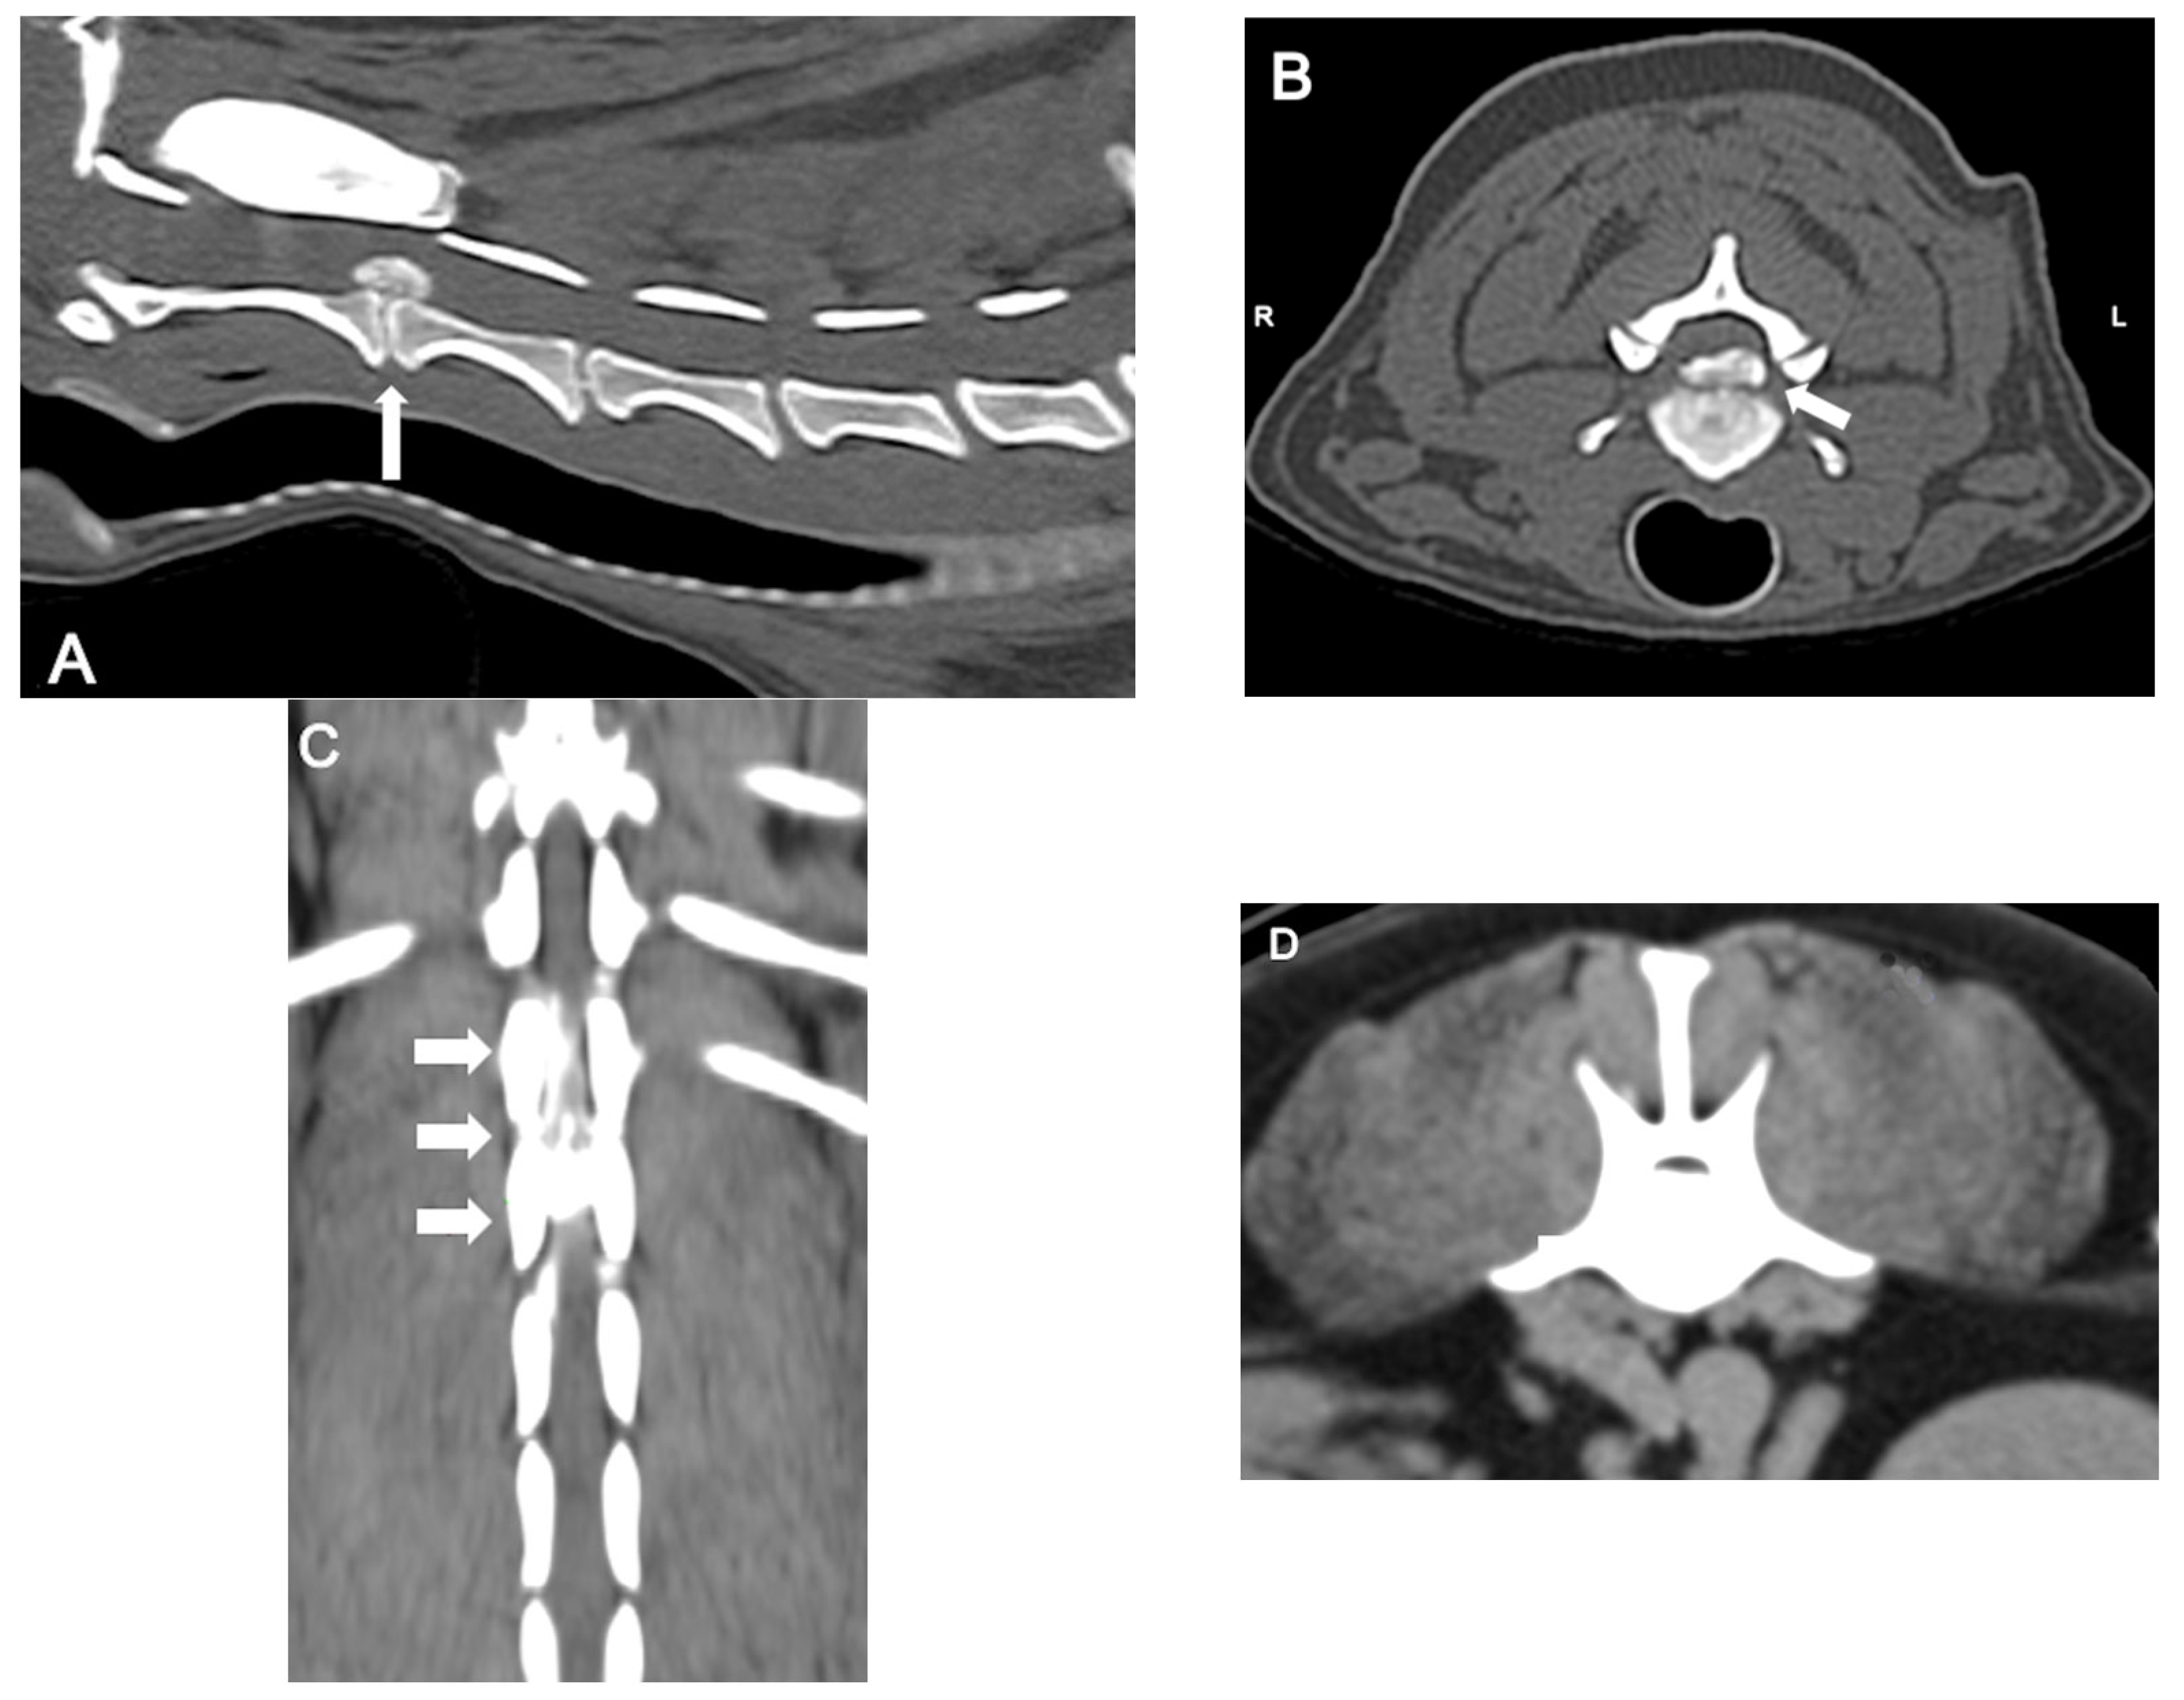

CT (Figure 4) is a rapid and lower-cost diagnostic tool compared to MRI. It offers a sensitivity of 81% to 100%, particularly in chondrodystrophic dogs with mineralized discs. Typical features of disc extrusion seen on CT include hyperattenuating material within the vertebral canal, loss of epidural fat, and distortion of the spinal cord. CT allows for distinguishing between acute and chronic mineralized disc material based on differences in radiodensity and morphology: acute extrusions typically appear as well-defined, dense, and homogeneous structures, while chronic material tends to be fragmented, irregular, or mixed with fibrous tissue. However, CT is reported to be less accurate in older dogs (>5 years) due to age-related disc mineralization that may occur without clinical signs, as well as in small dogs (<7 kg) because of lower spatial resolution and anatomical limitations that reduce contrast and image clarity; moreover, it does not provide details on the severity of intramedullary lesions, limiting its prognostic utility [38,42].

Figure 4.

Computed tomographic (CT) images showing several examples of the appearance of mineralized intervertebral disc extrusion in the vertebral canal. (A) Sagittal reconstructed non-contrast CT image showing a hyperattenuating mass suggestive of extruded disc material into the vertebral canal between C2-3 (arrow). (B) Transverse non-contrast CT image of the same patient showing a large hyperattenuating mass extending into the vertebral canal at the intervertebral disc C2-3 with a mild lateralization to the left (arrow). (C) Dorsal reconstructed post-contrast CT image showing an extensive heterogeneously hyperattenuating material (compared to the spinal cord), suggestive of an extruded degenerated disc mixed with epidural hemorrhage, compressing the spinal cord along the vertebral bodies of T13 and L1. (D) Transverse non-contrast CT image showing a large hyperattenuating mass disc extrusion occupying most of the vertebral canal at the intervertebral disc L1-L2.

CT is considered a first-line option in dogs with acute disc extrusion and degenerated discs because of its speed and affordability. It is particularly useful in young to middle-aged chondrodystrophic dogs. On the other hand, MRI is preferable in complex cases, as it identifies intramedullary lesions and concomitant pathologies. In conclusion, the selection of the imaging modality should be based on the clinical characteristics of the patient, the availability of the equipment, and the specific diagnostic objectives [44,45].